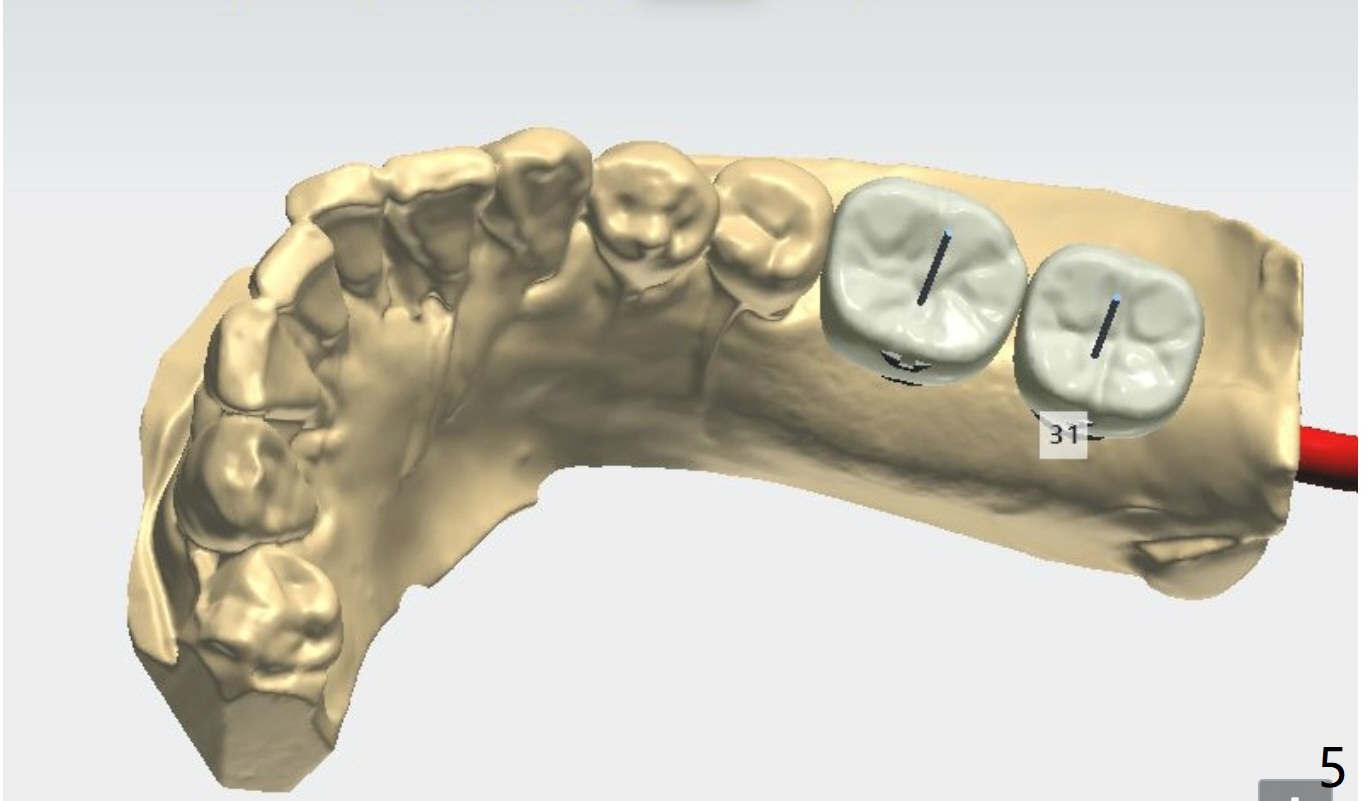

Lingual Access

Ridge top is flat with no deviation. If the keratinized gingiva is wide enough, no incision is required. If the patient uses water pik and torque is sufficient, place final abutments, fabricate provisional (preferably single units) and suture.